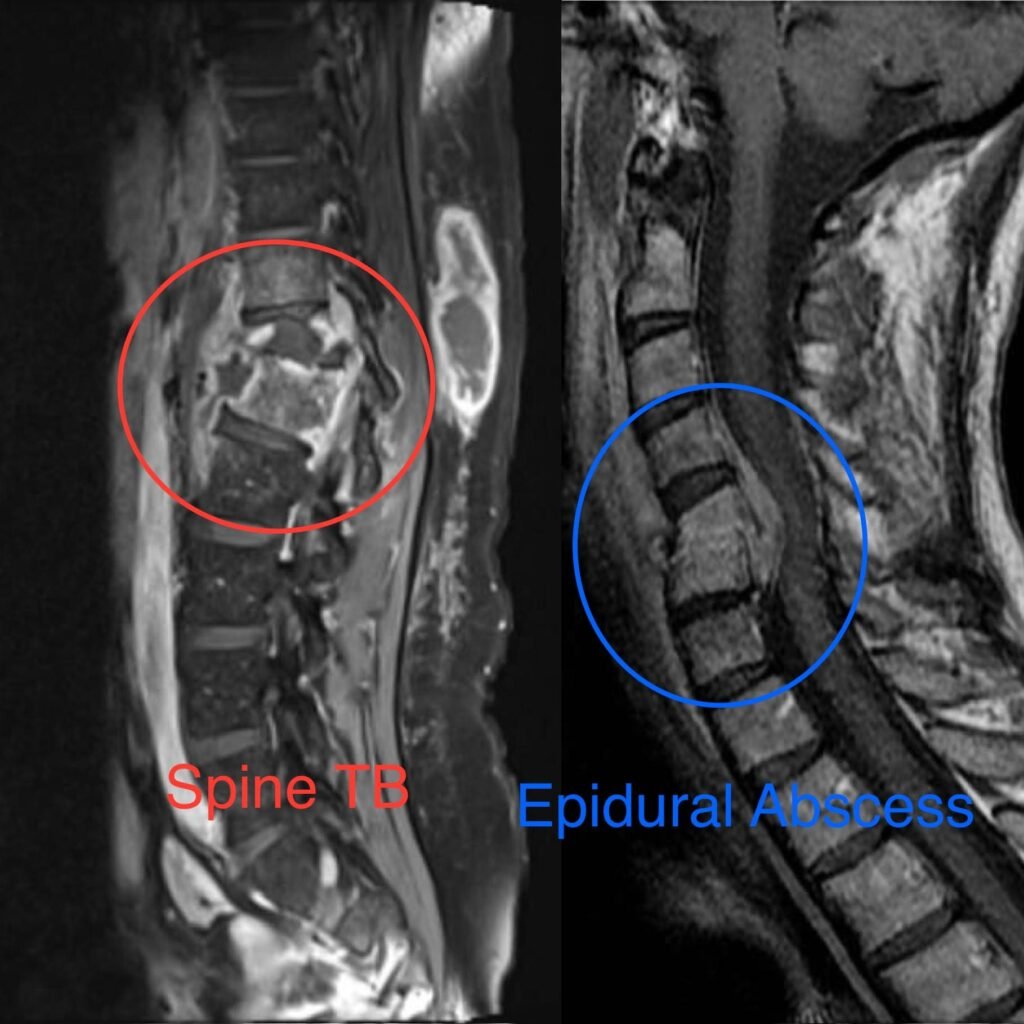

Spinal Infections

Spinal infections, also known as vertebral osteomyelitis or discitis, occur when bacteria or other pathogens infect the bones (vertebrae) or discs of the spine. These infections can be caused by bacteria, fungi, or viruses and can lead to inflammation, pain, and potential damage to the spinal structures.

• Diagnosis typically involves a physical examination, medical history, and imaging studies such as X-rays, CT scans, or MRI to evaluate the extent of the infection and identify any associated complications.

• Treatment options may include antibiotics (for bacterial infections), antifungal medication (for fungal infections), pain management, and in severe cases, surgery to drain abscesses, remove infected tissue, or stabilize the spine.